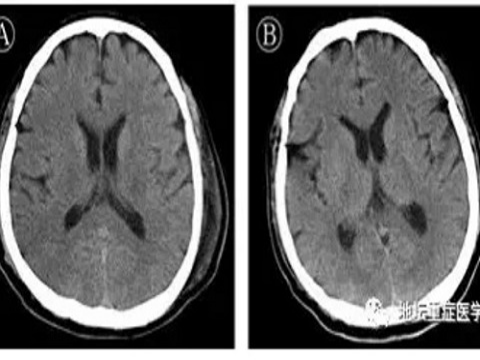

Tìm thấy bằng chứng đầu tiên về việc virus corona tấn công hệ thần kinh trung ương